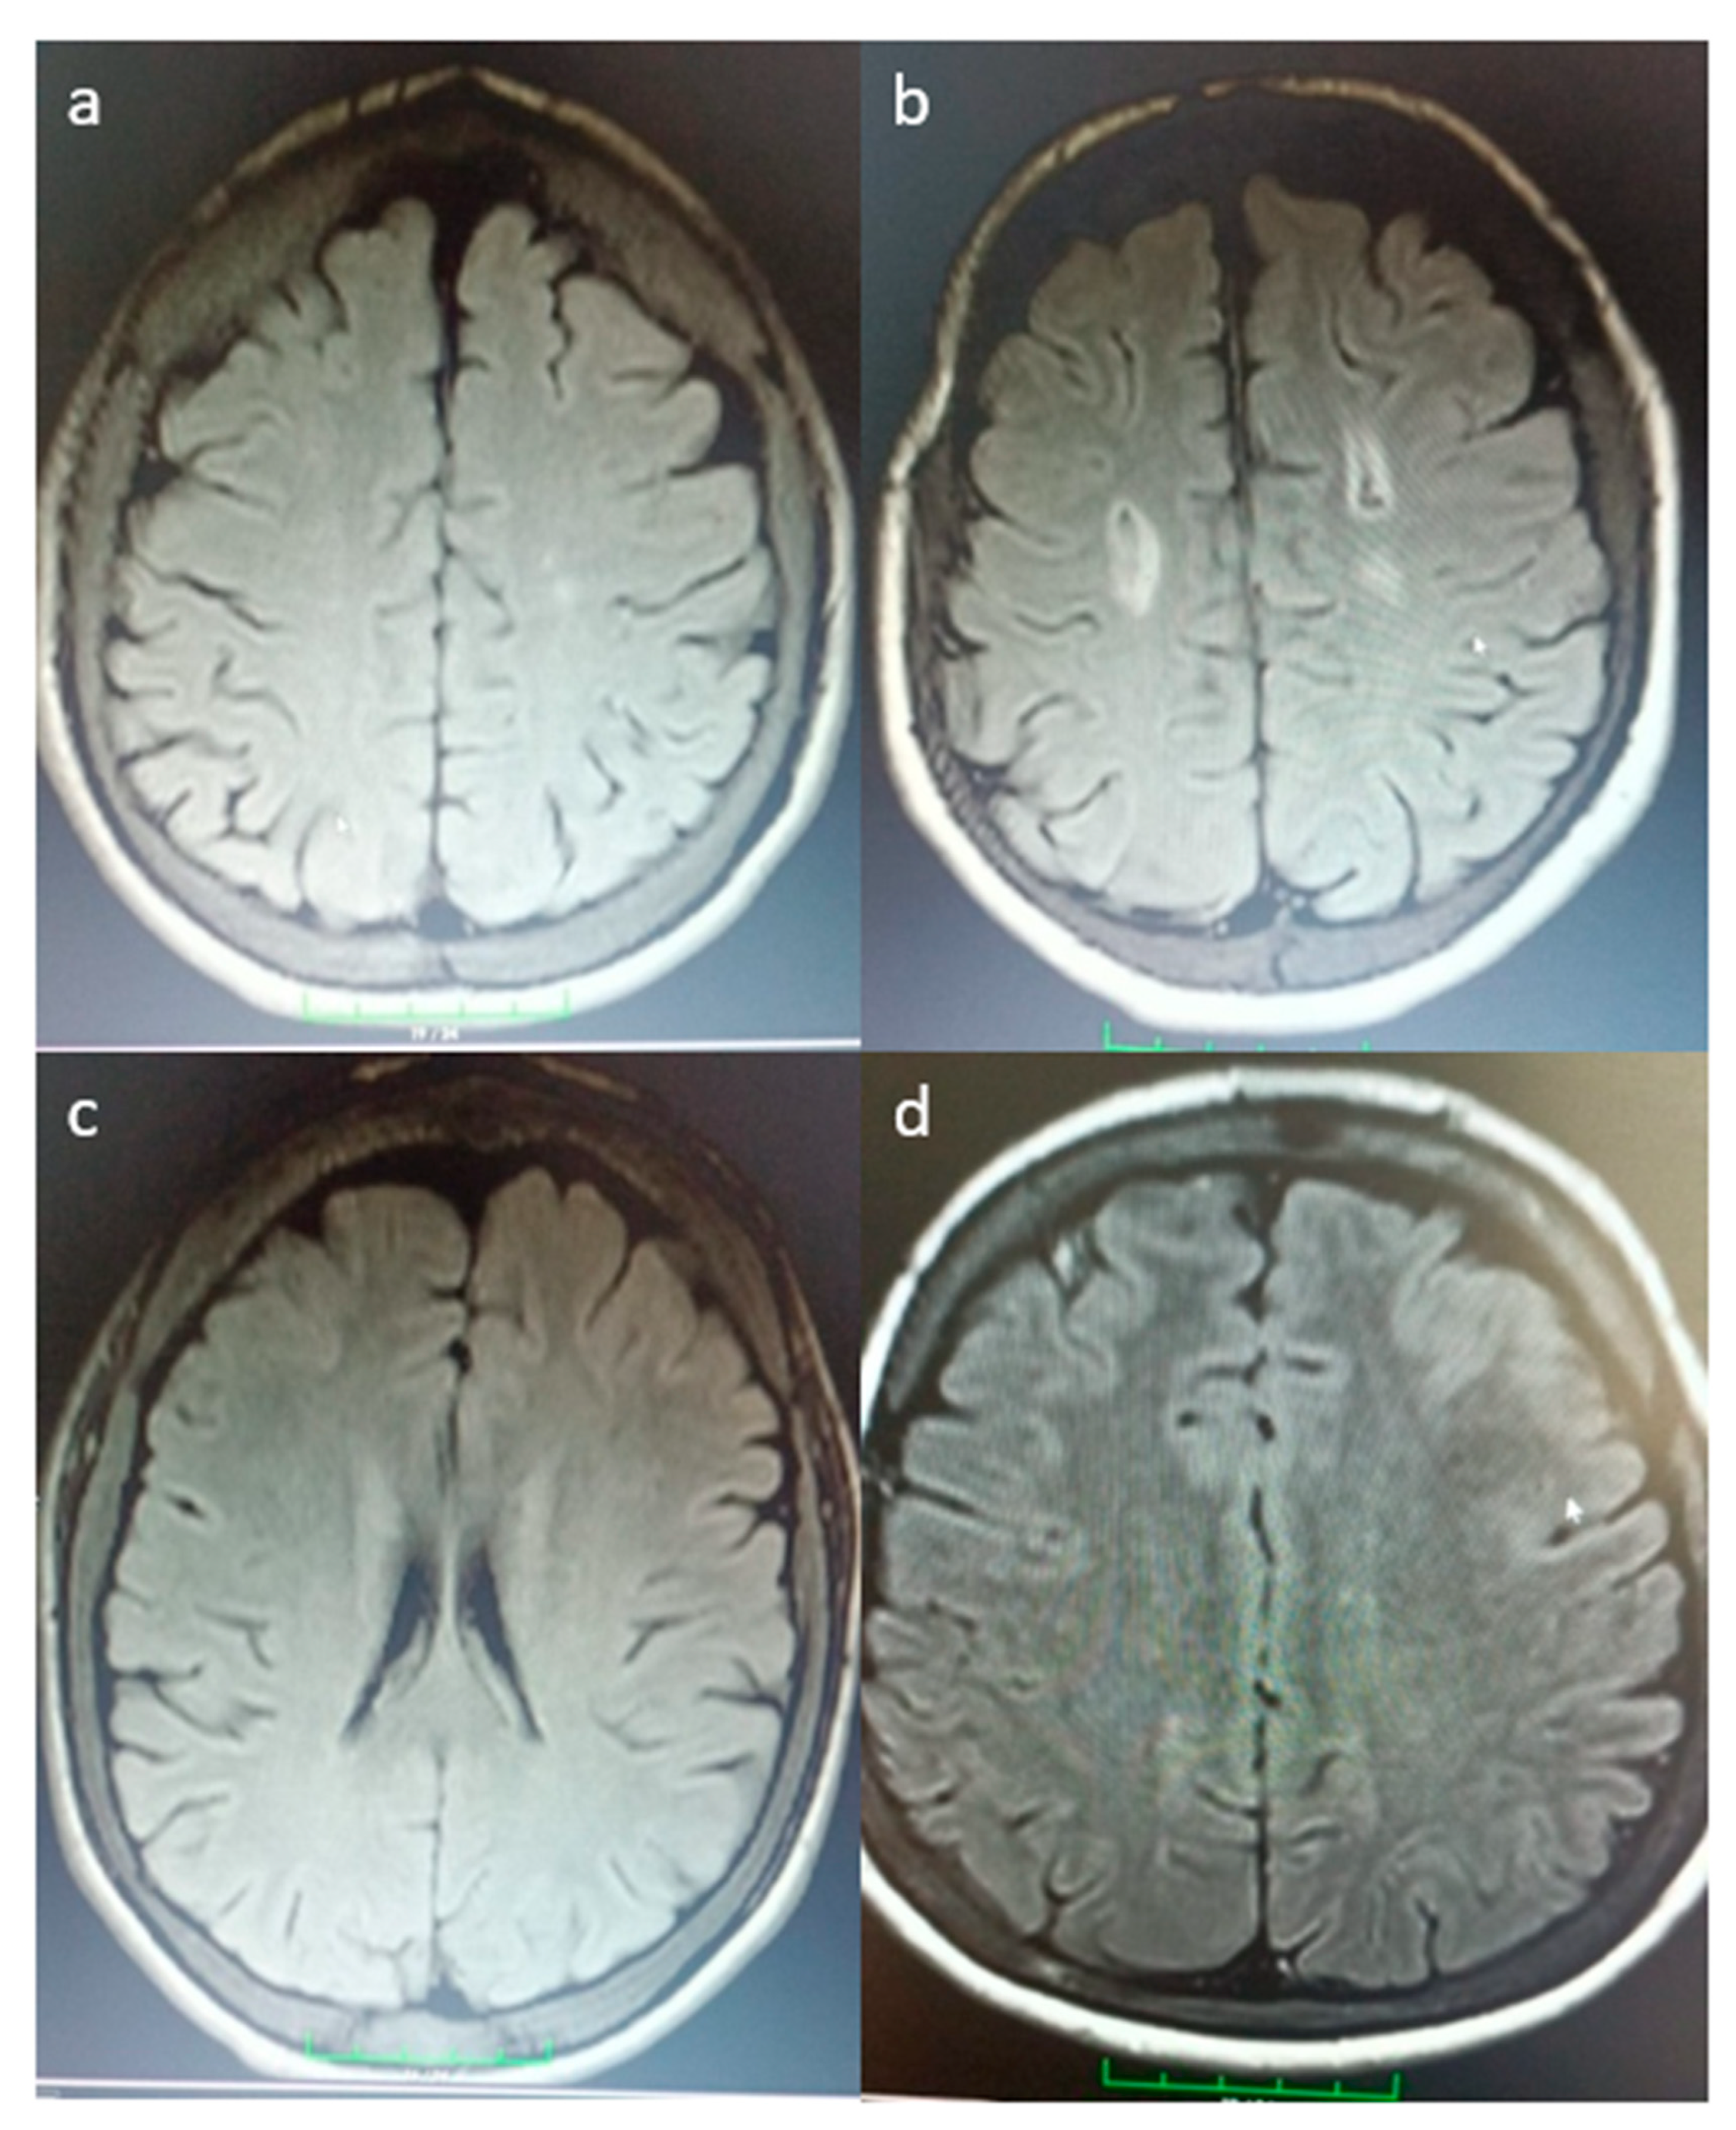

| MRI Ischemia | 5 (%19.2) | 7 (%30.4) | χ2 = 0.828, p = 0.363 |

| Ischemia Type | χ2 = 3.639, p = 0.303 | ||

| No ischemia | 21 (%80.8) | 16 (%69.6) | |

| Lacunar | 3 (%11.5) | 1 (%4.3) | |

| Small vessel | 1 (%3.8) | 2 (%8.7) | |

| Multiple | 1 (%3.8) | 4 (%17.4) | |